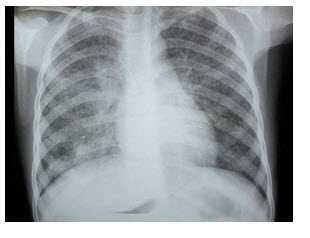

24、单项选择题

患者突发胸痛气急,呼吸困难,胸片如图,最可能的诊断为()

A.右侧肺大泡

B.右侧气胸

C.右侧中央型肺癌并阻塞性肺气肿

D.肺气肿

E.右肺肺炎